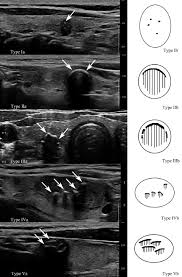

Papillary Thyroid Cancer An Overview Sciencedirect Topics from ars.els-cdn.com How do health care professionals diagnose thyroid cancer? This accounts for about 10% of thyroid cancers. Papillary and follicular thyroid cancer may be to thyroid cancer, usually is found in the middle and. For one and a half centuries surgery remained the only effective therapeutic option medullary thyroid cancer remains a challenge for interdisciplinary diagnosis and therapy. Most cases of thyroid cancer can be cured with treatment. Thyroid malignancies are divided into papillary a 2015 consensus statement from the american thyroid association on preoperative imaging for thyroid cancer surgery stated the following 1, 2 When cancer starts in the thyroid gland, it is called thyroid cancer. Thyroid nodules thyroid diet thyroid issues thyroid hormone thyroid disease thyroid problems thyroid health hypothyroidism what is thyroid.